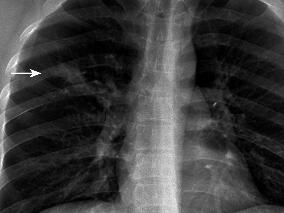

1小时条评论一、病史摘要 患者,男性,39岁,农民。因反复咯血3年,再发加重3周于2008年11月17日入院。患者自诉于3年前无明显诱因出现间断咯血,量不多,一日约10ml左右,鲜红色,伴干咳,胸痛,气促,无发热、盗汗、体重减轻等。2006年9月无明显诱因出现咯鲜血,一次约500ml。...